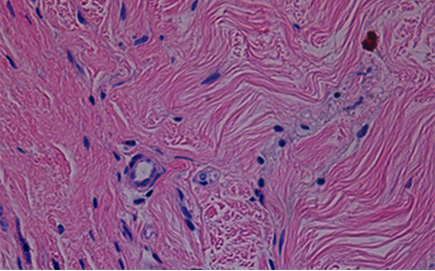

쥬브아셀은 인체 유래 무세포 진피(haDM) 기반으로 피부 안정성을 높이고

콜라겐 · 엘라스틴이 풍부해 피부 본연의 밀도와 탄력을 회복시킵니다.